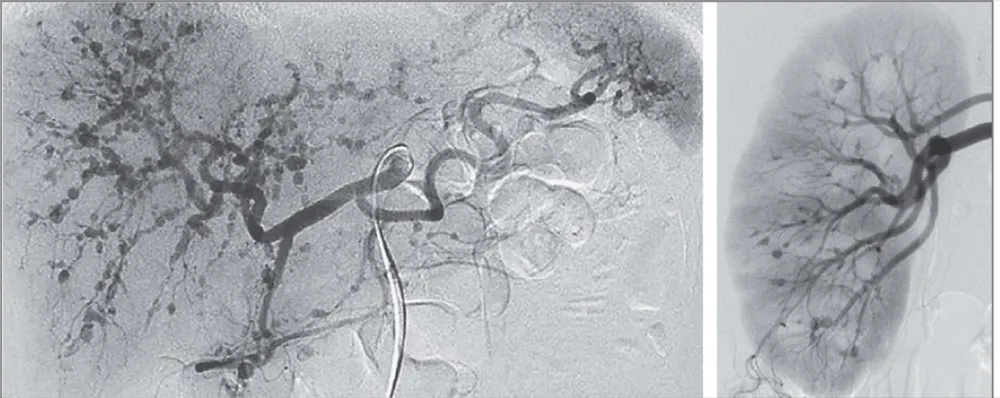

Um caso clínico muito bonito para entendersmo a fisiopatologia da hipertensão renovascular. Não deixa de conferir!

Já ouviu falar da Síndrome do roubo coronário-subclávio? e insuficiência cardíaca de alto-débito relacionada a FAV?